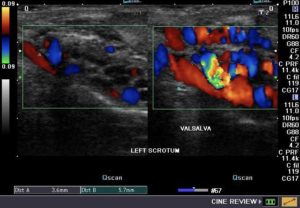

Υποκλινική

Η διάγνωση γίνεται μόνο με υπερηχογραφικό έλεγχο, χωρίς αυτή να είναι

ψηλαφητή ή ορατή στη δοκιμασία valsalva (αύξηση ενδοκοιλιακής πίεσης, βήχας, σφήξιμο κοιλιακών τοιχωμάτων). -

Η επιβεβαίωση γίνεται με υπερηχογραφικό έλεγχο (έγχρωμο triplex).